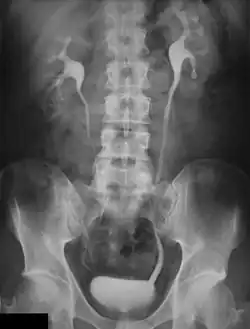

Pyelogram

Pyelogram (or pyelography or urography) is a form of imaging of the renal pelvis and ureter.[1]